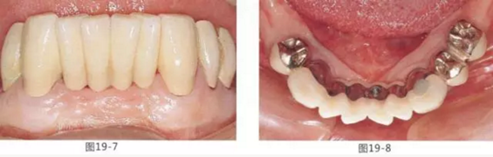

圖19-7 佩戴最終修復5年后的唇頰側(cè)面照。

圖19-8 同時期下側(cè)咬合面照。